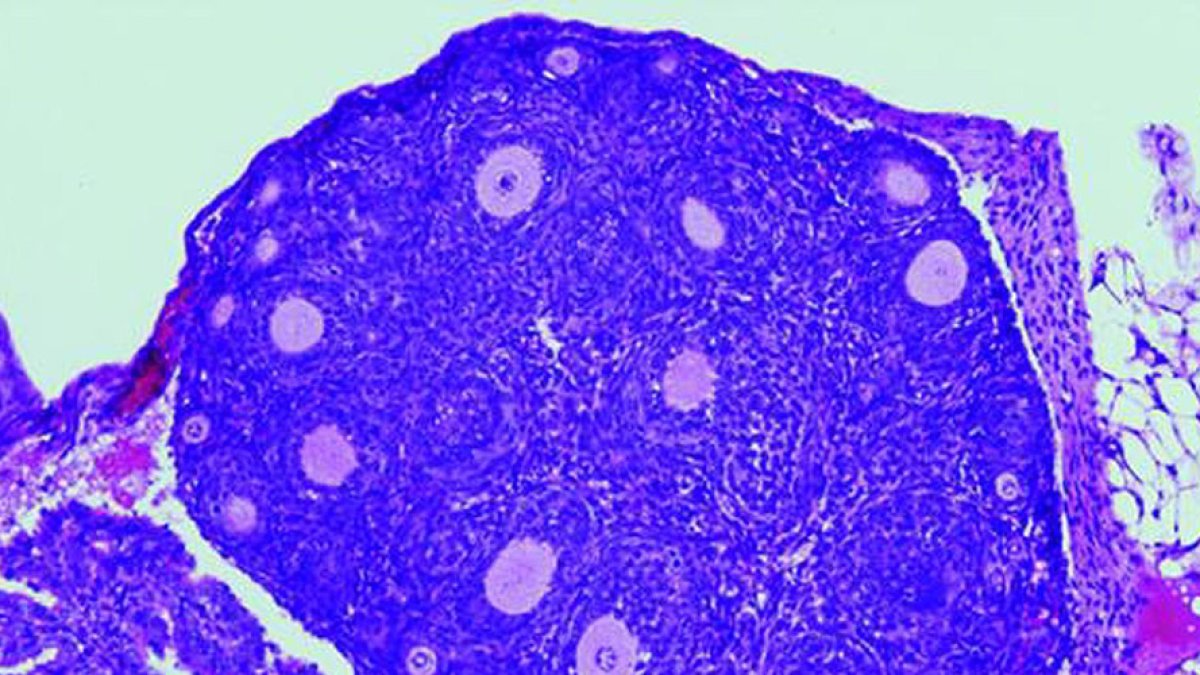

Los neurocientíficos descubrieron que dos áreas del cerebro de los ratones, el córtex retrosplenial (RSP) y el colículo superior (SC), forman un circuito que codifica la dirección hacia un refugio, lo que les permite orientarse con precisión y escapar a un lugar seguro.Cuando suena una alarma de incendios, instintivamente sabemos cómo salir de la habitación para ponernos a salvo, lo que se debe a que el cerebro mantiene continuamente un registro de dónde está la salida y lo hace de forma inconsciente.

El equipo trabajó con ratones a los que conectó unos electrodos en miniatura para grabar simultáneamente en dos regiones del cerebro - RSP y SC- mientras se les presentaba un sonido amenazador.

El RSP calcula la dirección del refugio y luego envía esta información al SC, que utiliza esta dirección para girar la cabeza del ratón.

Sin embargo, cuando se perturbaba la conexión entre estas dos regiones, impidiendo que el RSP hablara con el SC, el ratón corría en una dirección aleatoria cuando se asustaba.

Branco explicó que el circuito RSP-SC es una vía fundamental para saber dónde está el refugio y orientarse hacia él. Una conexión que a nivel celular está cableada de una manera inteligente.

En sus experimentos, los neurocientíficos incluyeron un segundo refugio idéntico pero con la entrada cerrada y comprobaron que el RSP representa tanto el refugio cerrado como el abierto, pero el SC solo el abierto.

Una posible explicación es que el RSP representa muchos objetivos posibles y el SC selecciona el más importante para el contexto concreto, en este caso el refugio abierto que confiere seguridad.